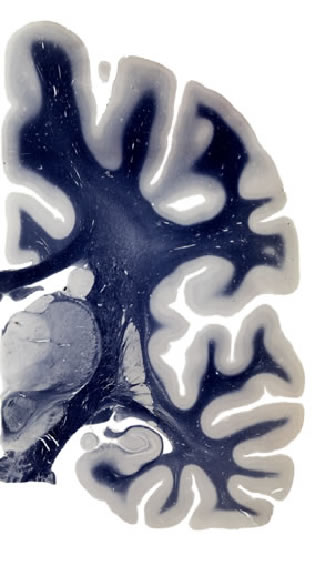

Frontal sections (Nissl) from the Atlas Brain: Gallery Slice Single

20,9 mm

Slice ID: r3-0615

Plate NR: ca 37-38

Position: 20,9 mm